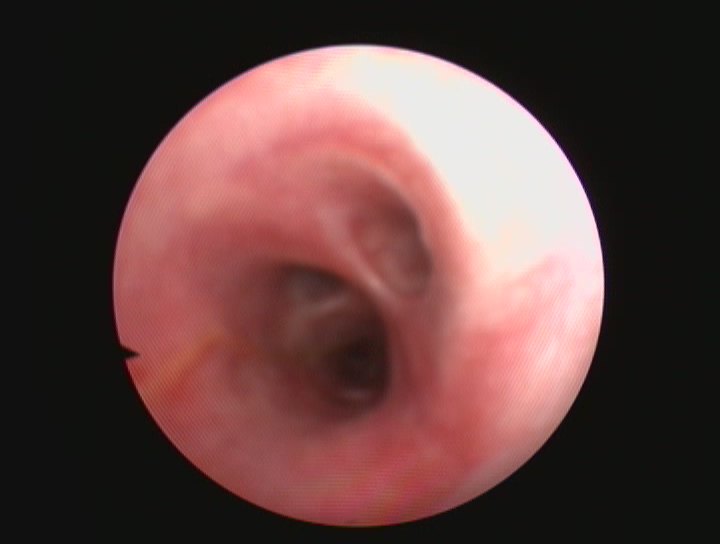

ENDOSCOPIA

L'Endoscopia è una branca della diagnostica per immagini che permette di ottenere immagini fotografiche e filmati attraverso l'utilizzo di piccole telecamere.

L'Ospedale degli animali è in grado di eseguire esami endoscopici, quali gastroduodenoscopia, colonscopia (con prelievi bioptici) ed endoscopia delle vie respiratorie comprensive di BAL, brushing (per la citologia diagnostica ) e biopsia. La videondoscopia è una tecnica rapida e sicura e che spesso si coniuga con la chirurgia delle vie respiratorie.